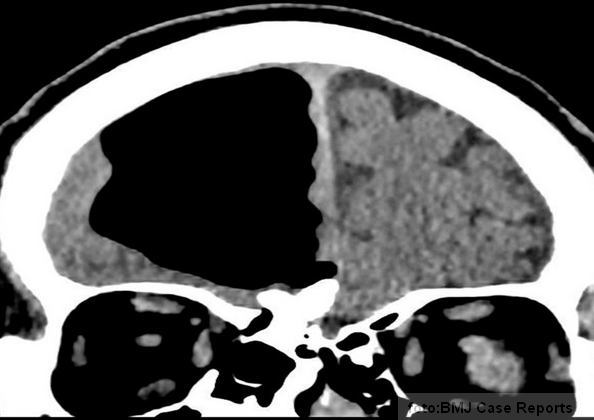

No, kada je muškarcu urađena kompjuterska tomografija i magnetna rezonanca mozga, medicinski tim je u čeonom režnju glave otkrio vazduhom ispunjenu šupljinu, prečnika čak devet centimetara!

Usput su otkrili i benigni tumor, tačnije koštanu izraslinu u nazalnom sinusu, koja je izgleda kriva za sve.

Iako snimci deluju kao da ovom čoveku fali parče mozga, lekar ističe da to nije slučaj – verovatnije je da je vazduh sabio mozak.